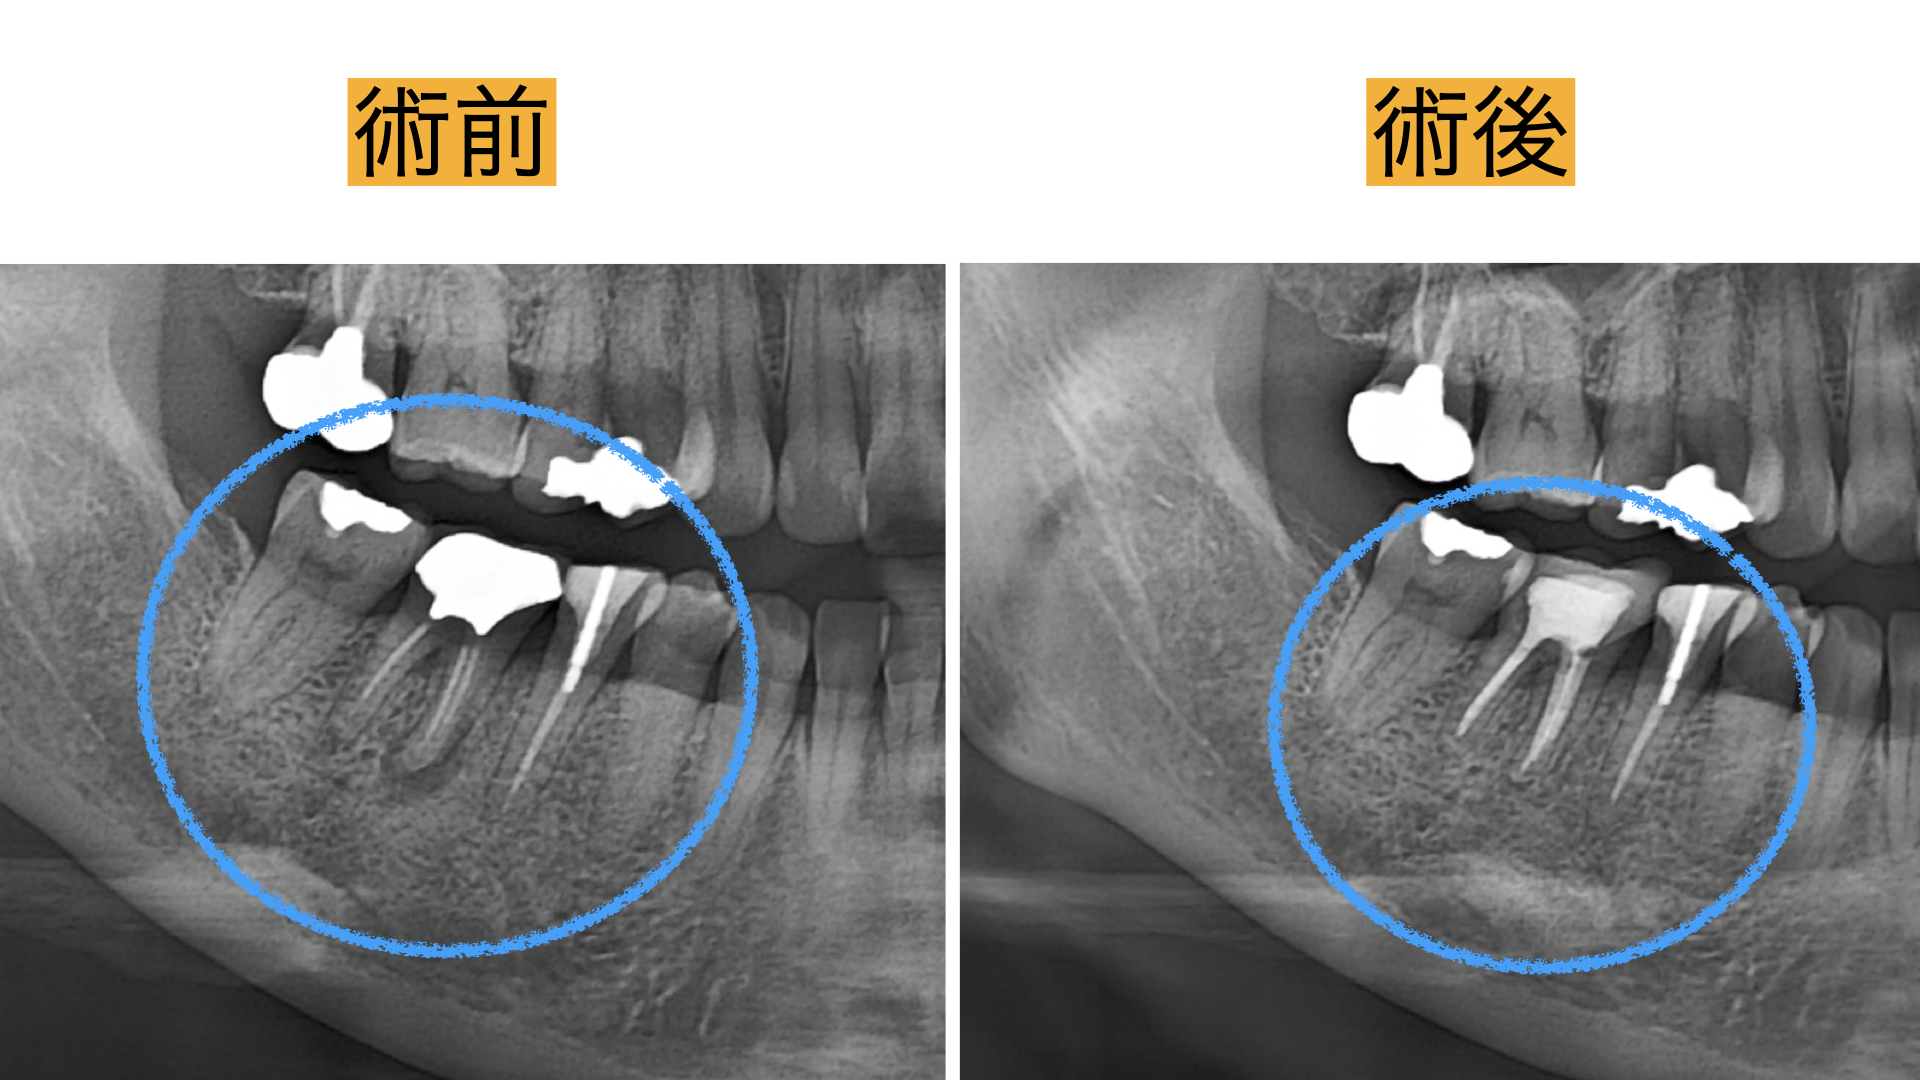

3D診断(CT)

歯科用CTは3次元の立体画像で診断することが可能です。通常のXrayは2次元の写真のため、 根管治療において複雑な根管形態を正確に把握できません。 CTでの根管形態の把握は、根管治療において必須です。

術後

術直後から痛み、腫れは、解消し2年間の経過観察も問題なく過ごせましたとのことでした。 レントゲンで骨の回復が確認とれ、非常に驚かれておりました。